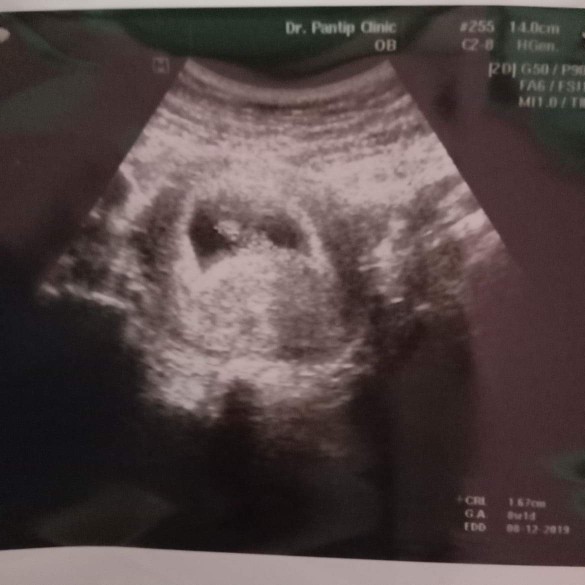

9 week เห็นแล้วค่ะ